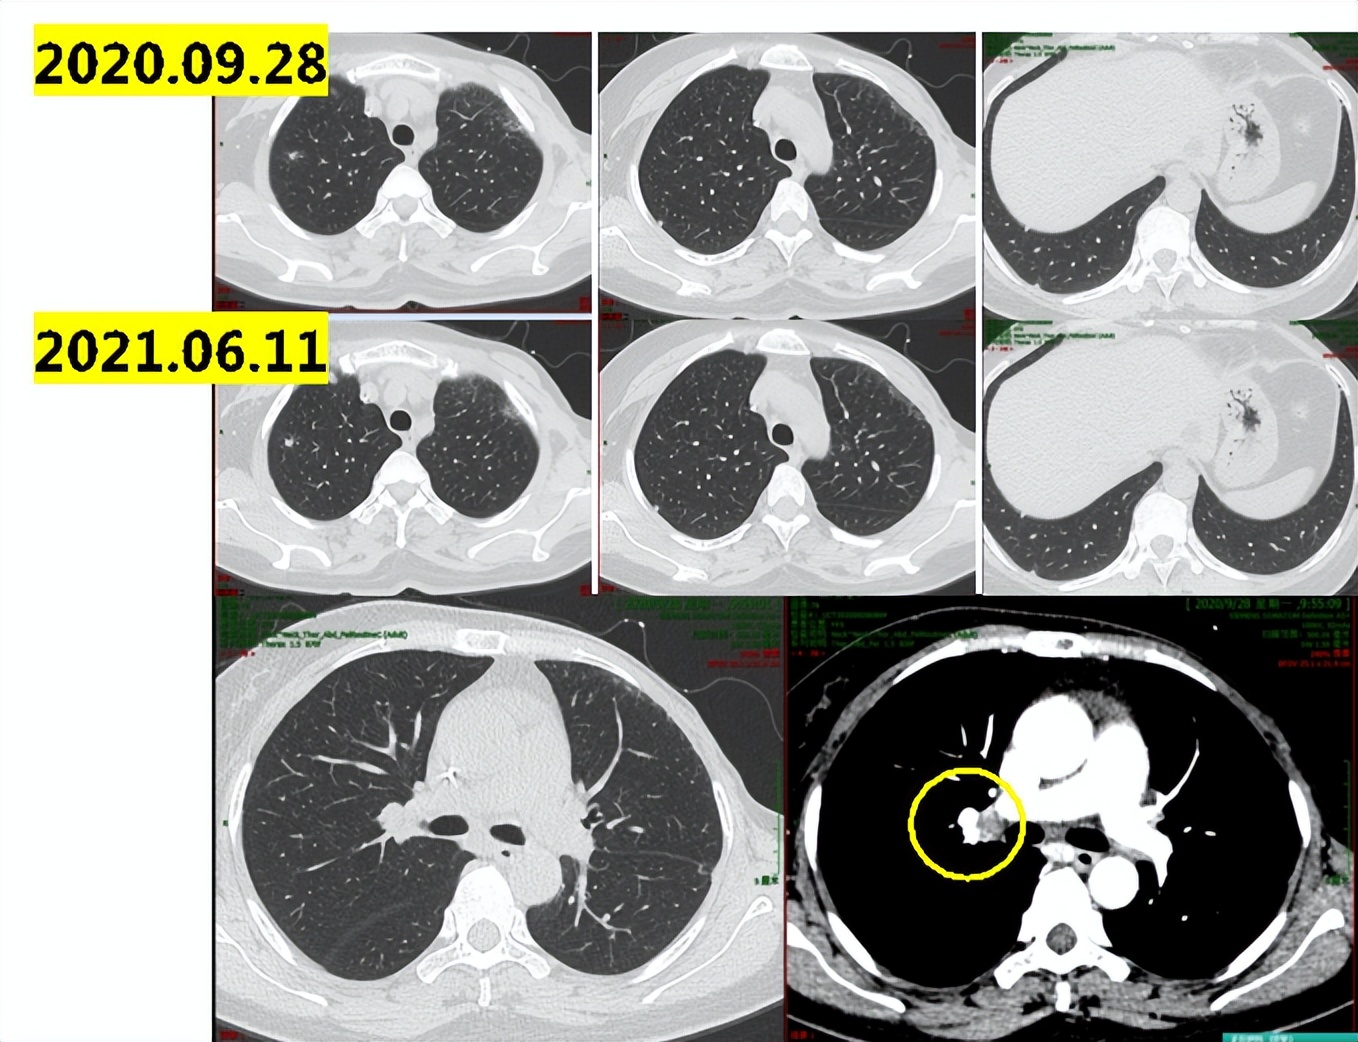

讨论意见:患者转移病灶瘤负荷低,双肺和纵隔转移数目小于5个,最大直径1.3cm,无内脏危象,建议CDK4/6*制剂抑**联合内分泌治疗。然而进口CDK4/6*制剂抑**患者仍因经济原因无法负担。患者情况符合国产CDK4/6*制剂抑**临床试验入组标准,建议入组:XZP-3287(吡罗西尼)治疗中国晚期恶性实体瘤受试者的多中心、开放性Ⅰ/Ⅱ期临床研究。

执行情况及治疗结局:

2021.06-2021.09入组:XZP-3287(吡罗西尼)治疗中国晚期恶性实体瘤受试者的多中心、开放性Ⅰ/Ⅱ期临床研究,2021.09初患者开始出现胸闷气喘,2021.09.17肺部CT示:双肺下叶炎性病变,双肺下叶小叶间隔增厚,考虑间质性病变;双肺散在结节影,部分同前相仿,部分较前新发,考虑转移可能;心包积液,较前增多。示双肺及叶间裂胸膜处多发小结节,较前新发,考虑病情进展(图1-4)。

图1-4